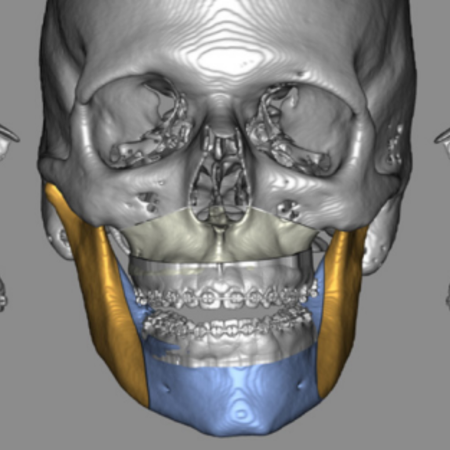

Objetivo: Este trabalho teve como objetivo comparar um novo método de oclusão digital automática, para planejamento cirúrgico virtual em cirurgia ortognática, com um método de oclusão digital e outro método manual convencional. Metodologia: Foi realizado um estudo de validação, com uma amostra de conveniência composta por 20 pacientes, sendo 7 do sexo masculino (35%) e 13 do sexo feminino (65%). Dois avaliadores, de forma independente, determinaram a oclusão final de cada...

Objective: This study aims to compare a new automatic digital occlusion method, for virtual surgical planning in orthognathic surgery, with a conventional digital method and a manual occlusion method. Methodology: A validation study was carried out, with a convenience sample consisting of 20 patients, 7 males (35%) and 13 females (65%). Two evaluators independently determined the final occlusion of each patient, using a conventional manual method, a digital method and an automatic digital...